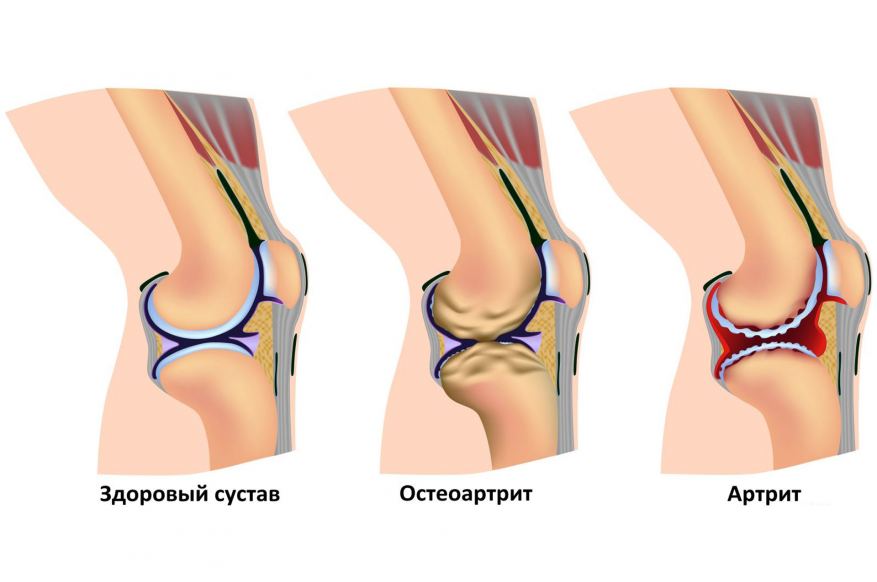

При заболеваниях суставов и позвоночника (остеохондроз, радикулит, артрит, артроз и др.). При лечении этих видов заболеваний рекомендуется сочетание ежедневного употребления в пищу настоянной на шунгите воды, с регулярным применением шунгитовых ванн, компрессов и специального шунгитного массажа стоп.

При комплексном лечении улучшается микроциркуляция крови и питание тканей в области больного сустава, значительно снижаются болевые ощущения, увеличивается подвижность суставов.

Ее можно пить при заболеваниях опорно-двигательного аппарата: артрите, остеартрите, варикозном расширении вен.